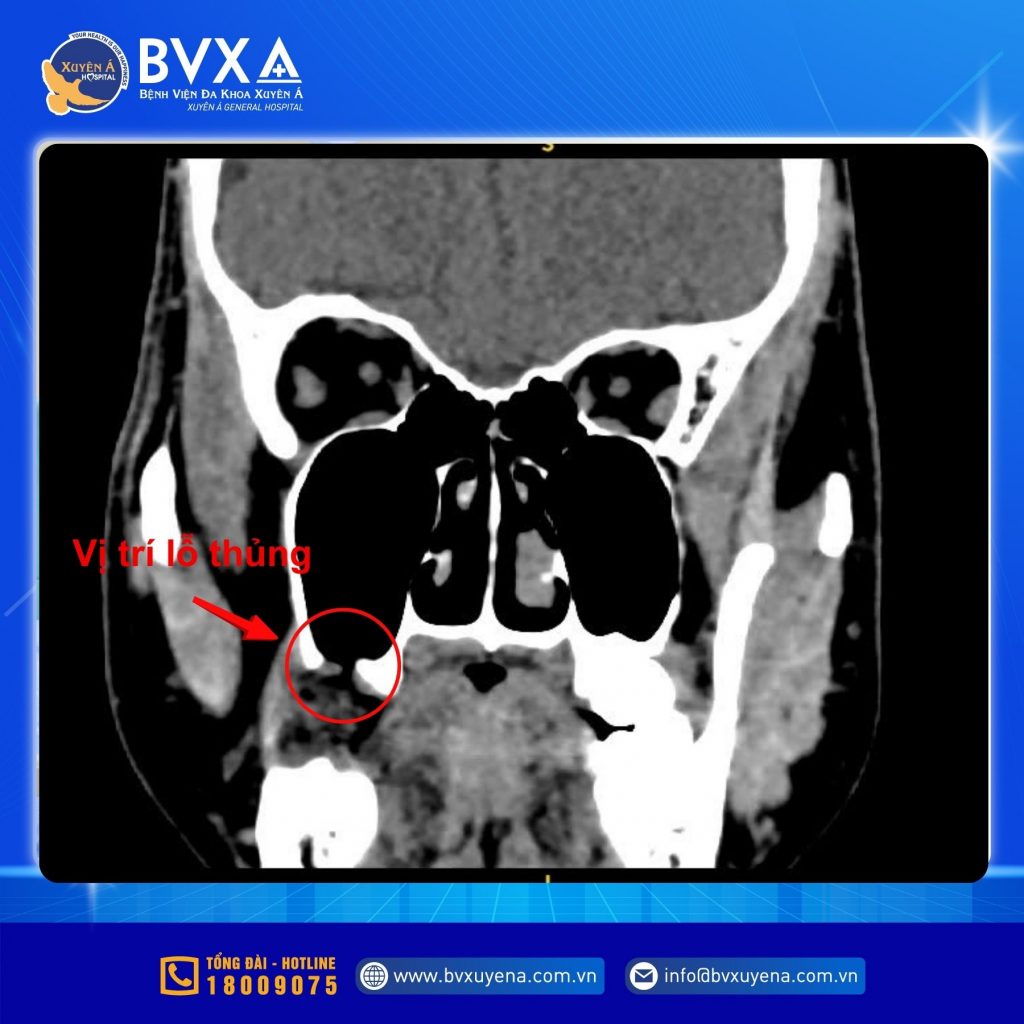

Tại Bệnh viện Đa khoa Xuyên Á – Long An, qua thăm khám và chụp CT scan hàm-mặt, BS.CKI. Phạm Ngọc Thái Sơn – Phụ trách Khoa Liên Chuyên Khoa phát hiện một lỗ thủng vùng răng số 18 thông vào xoang hàm.

Hình ảnh CT cho thấy bệnh nhân thủng xoang hàm sau khi nhổ răng khôn

Chính lỗ thông này khiến nước uống trào lên mũi và gây viêm xoang mạn tính tái phát.